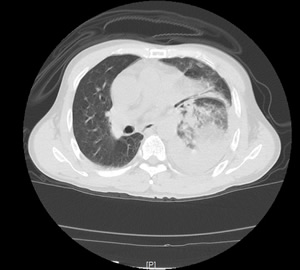

患者左下肺炎症、左侧胸腔积液、纵隔右移 患者部分肠管及胃疝到左侧胸腔